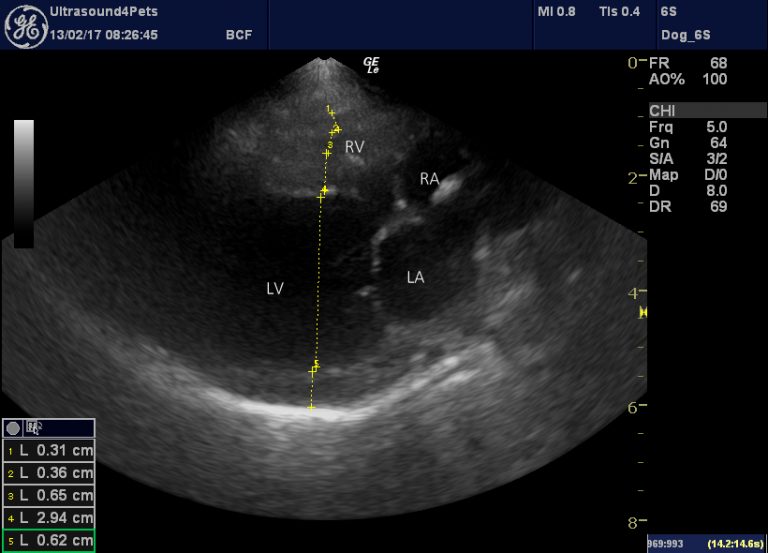

From www.vetpracticesupport.com

Canine patent ductus arteriosus (PDA) echocardiography Vet Practice Pda Meaning Veterinary — patent ductus arteriosus (pda) is one of the most common congenital heart defects in dogs, accounting for approximately 10 to 30. learn about patent ductus arteriosus (pda), a congenital heart defect in dogs and cats that causes blood to shunt from the aorta to the lungs. — a patent ductus arteriosus (pda) is an arterial shunt. Pda Meaning Veterinary.

Canine patent ductus arteriosus (PDA) echocardiography Vet Practice Pda Meaning Veterinary The ductus arteriosus is a. learn about patent ductus arteriosus (pda), a birth defect that causes abnormal blood flow in the heart and lungs. — a patent ductus arteriosus (pda) is an arterial shunt between the pulmonary artery and the aorta that is. patent ductus arteriosus (pda) is one of the most common congenital heart defects in. Pda Meaning Veterinary.